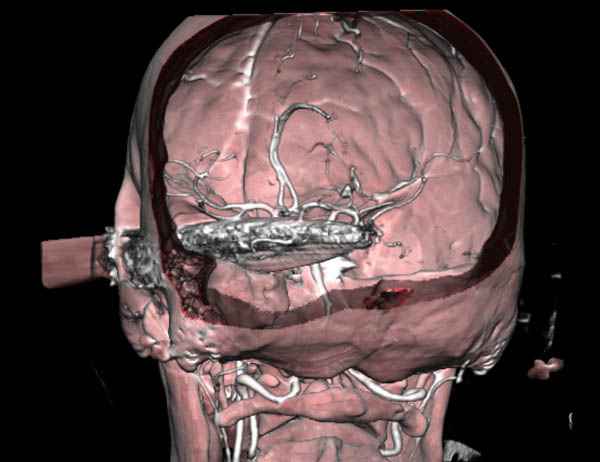

По протоколу сделаны все необходимые исследования: рентген, ангиограмма с 3Д реконструкцией, где обнаружили что все жизненно важные сосуды не задеты, даже некоторые "сидят" изгибаясь на ноже.

Одним махом нож удалить не удалось, пришлось раскачать и потом двумя руками удалили нож. Рана без кровотечения, обработана и зашита.